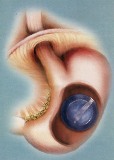

Новая операция для похудения в Москве

Операция SADI является одновременно и рестриктивной и мальабсорбтивной. Данная операция предлагает сильный и стабильный результат в отношении снижении веса, диабета и липидных нарушений. »подробнее